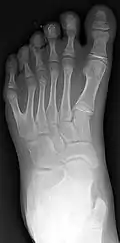

كثرة الأصابع

كثرة الأصابع (بالإنجليزية: Polydactyly) ( من الاغريقية πολύς (polys) تعني " عديد "، و άκτυλος (daktylos)تعني " اصبع")،[1] ويعرف أيضاً بالعنش، هو تشوه خِلقي جسدي في البشر والكلاب والقطط ذات أصابع القدم أو اليد الزائدة.[2] عديد الأصابع هو معاكس لقلة الأصابع(عدد أقل من أصابع القدم أو اليد) .

التصنيف تم باستخدام التصوير بالأشعة السينية لرؤية بنية العظم.[14]